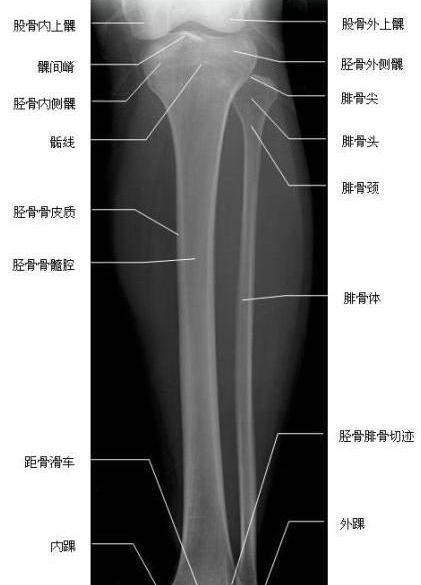

胫腓骨侧位-x线-解剖图片

填图题 | 胫腓骨解剖

胫腓骨正位—x线

胫腓骨正侧位

胫腓骨正侧位图片

正常胫腓骨x线正侧位

胫腓骨解剖

胫腓骨解剖图